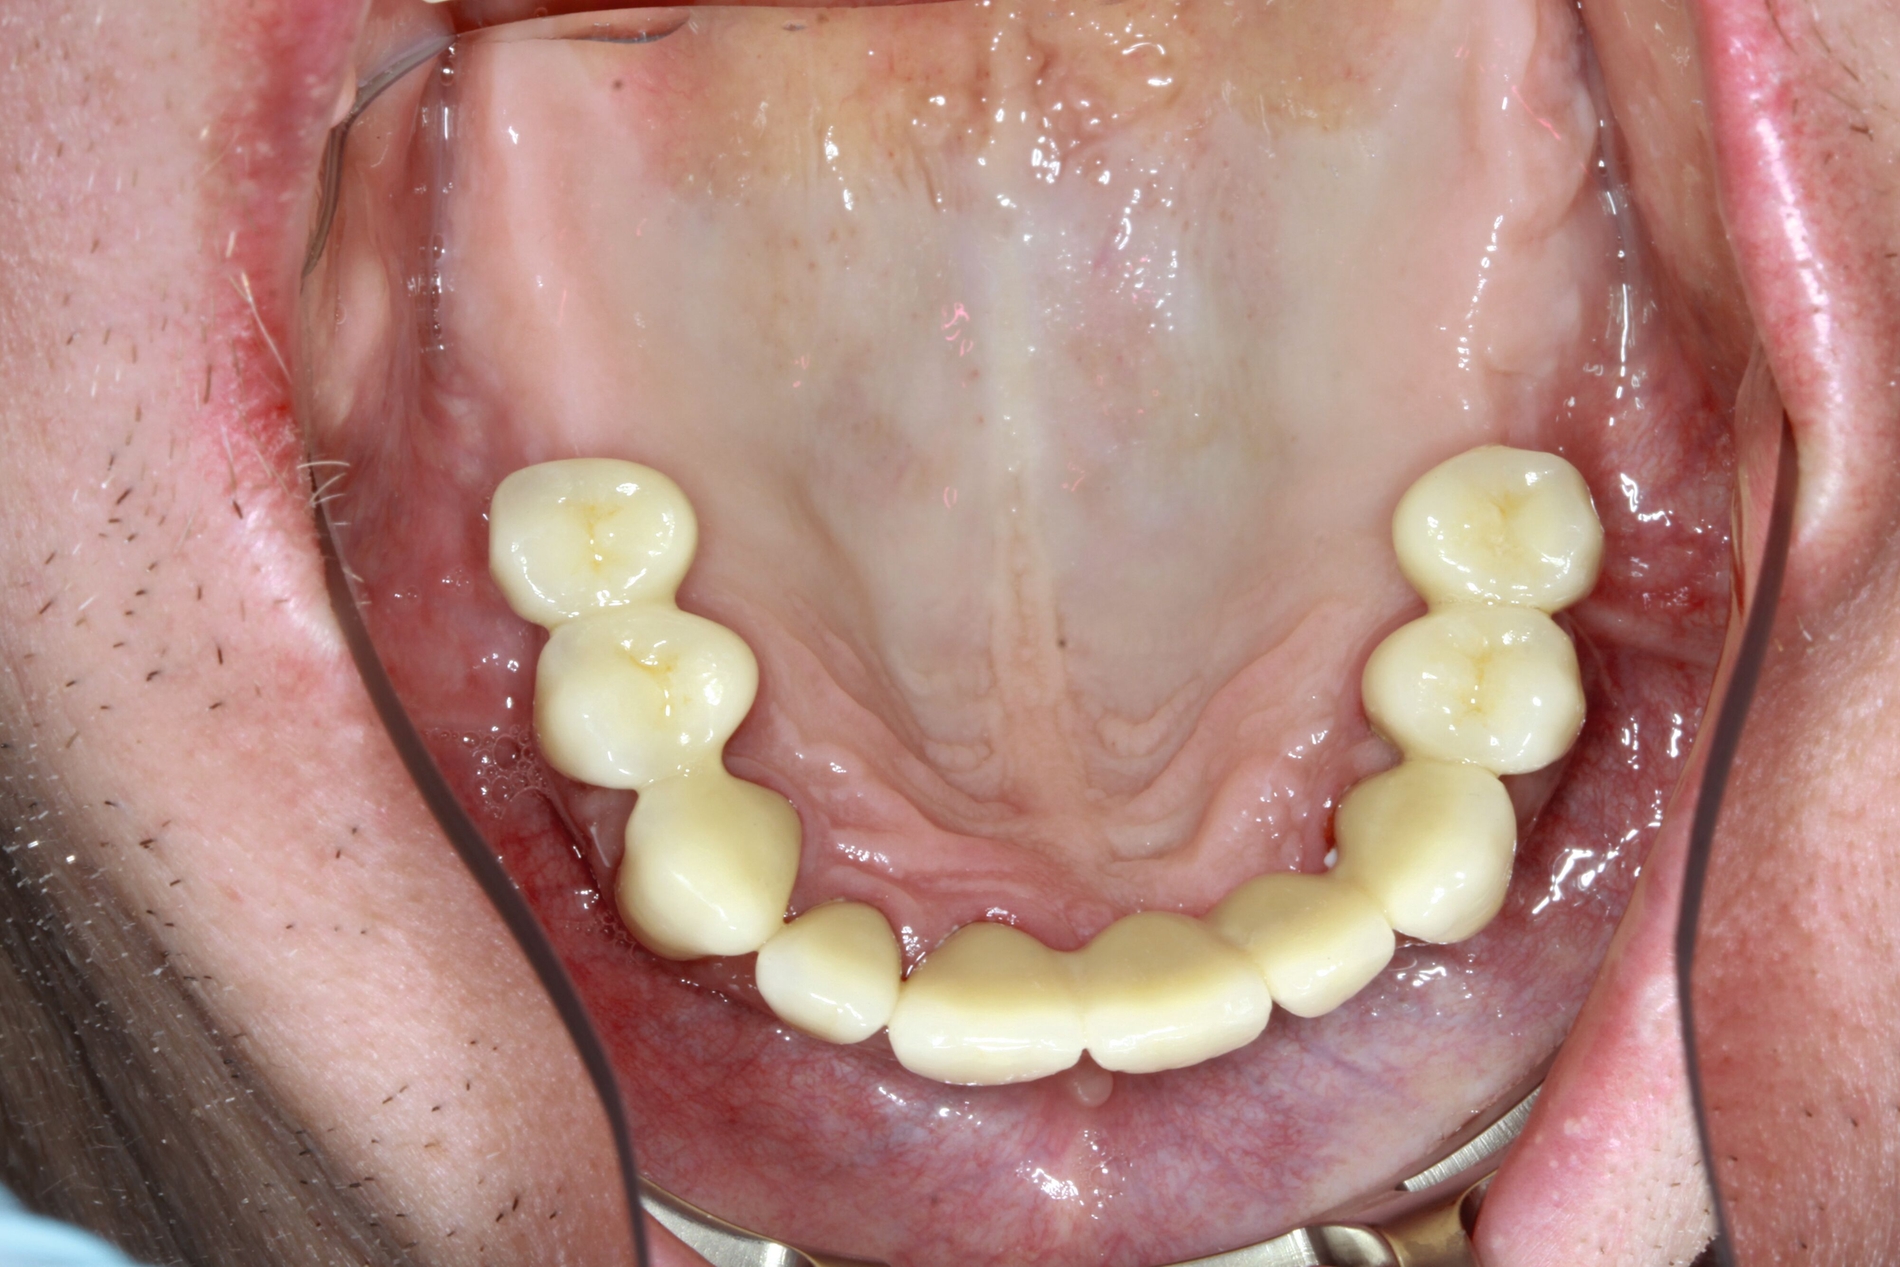

So kann die prothetische Versorgung bilateral verkürzter Zahnreihen erfolgen durch:

Molarenersatz mit abnehmbarem Zahnersatz, verankert über Klammern, Doppelkronen oder Geschiebe

Implantatprothetischen Molarenersatz (zahnbezogen, implantatgetragene Brücken, Verbundbrücken)

Belassen der verkürzten Zahnreihe, abhängig vom Lebensalter der Patienten mit einer Prämolarenokklusion, einer reduzierten Prämolarenokklusion oder einer reinen Frontzahnokklusion bei sehr betagten Patienten

Wiederherstellung einer Prämolarenokklusion mit festsitzendem Zahnersatz, konventionell oder implantatprothetisch